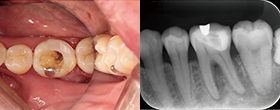

Case2 直線根管

• CC「左下奥違和感」主訴に来院

左下6遠心根に透過像認める

• インレー除去

透過像に一致した部位にサイナストラクト認める

• コンポジットレジンにて隔壁作成

• 作業長確認

最終拡大#30/.04テーパー